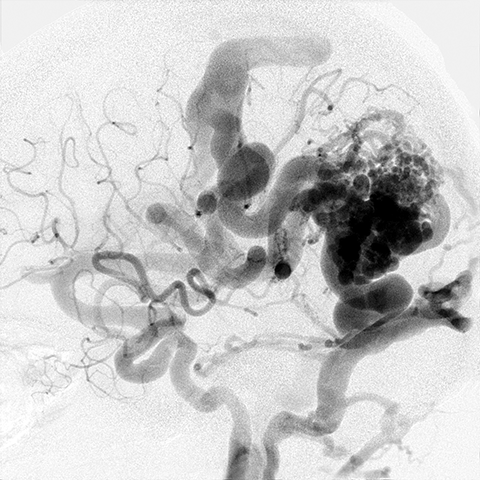

44 year old with Hereditary Hemorrhagic Telangiectasia presents with a headache. [2 of 3]